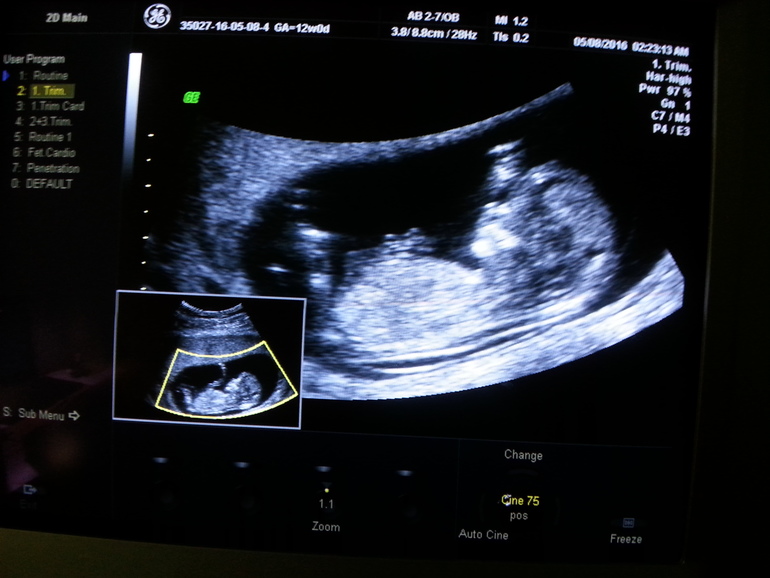

Теперь немного по цифрам)

Срок по М 12+1

КТР 63 мм

ЧСС 154 уд/мин

ТВП 1,8 мм

Носовая кость 1,9 мм

По КТР плода беременность 12+5

В этот раз после осмотра попросила узистку, чтобы она мне выбрала ракурс и я смогла сфотографировать малыша на экране, так что выкладываю фото. Сверху-это то, что видела я, а снизу то, что видела врач на мониторе) Кстати предположили девочку, но я пока не хочу акцентировать на этом внимание, ведь для меня самое главное, чтобы малыш рос и родился здоровым